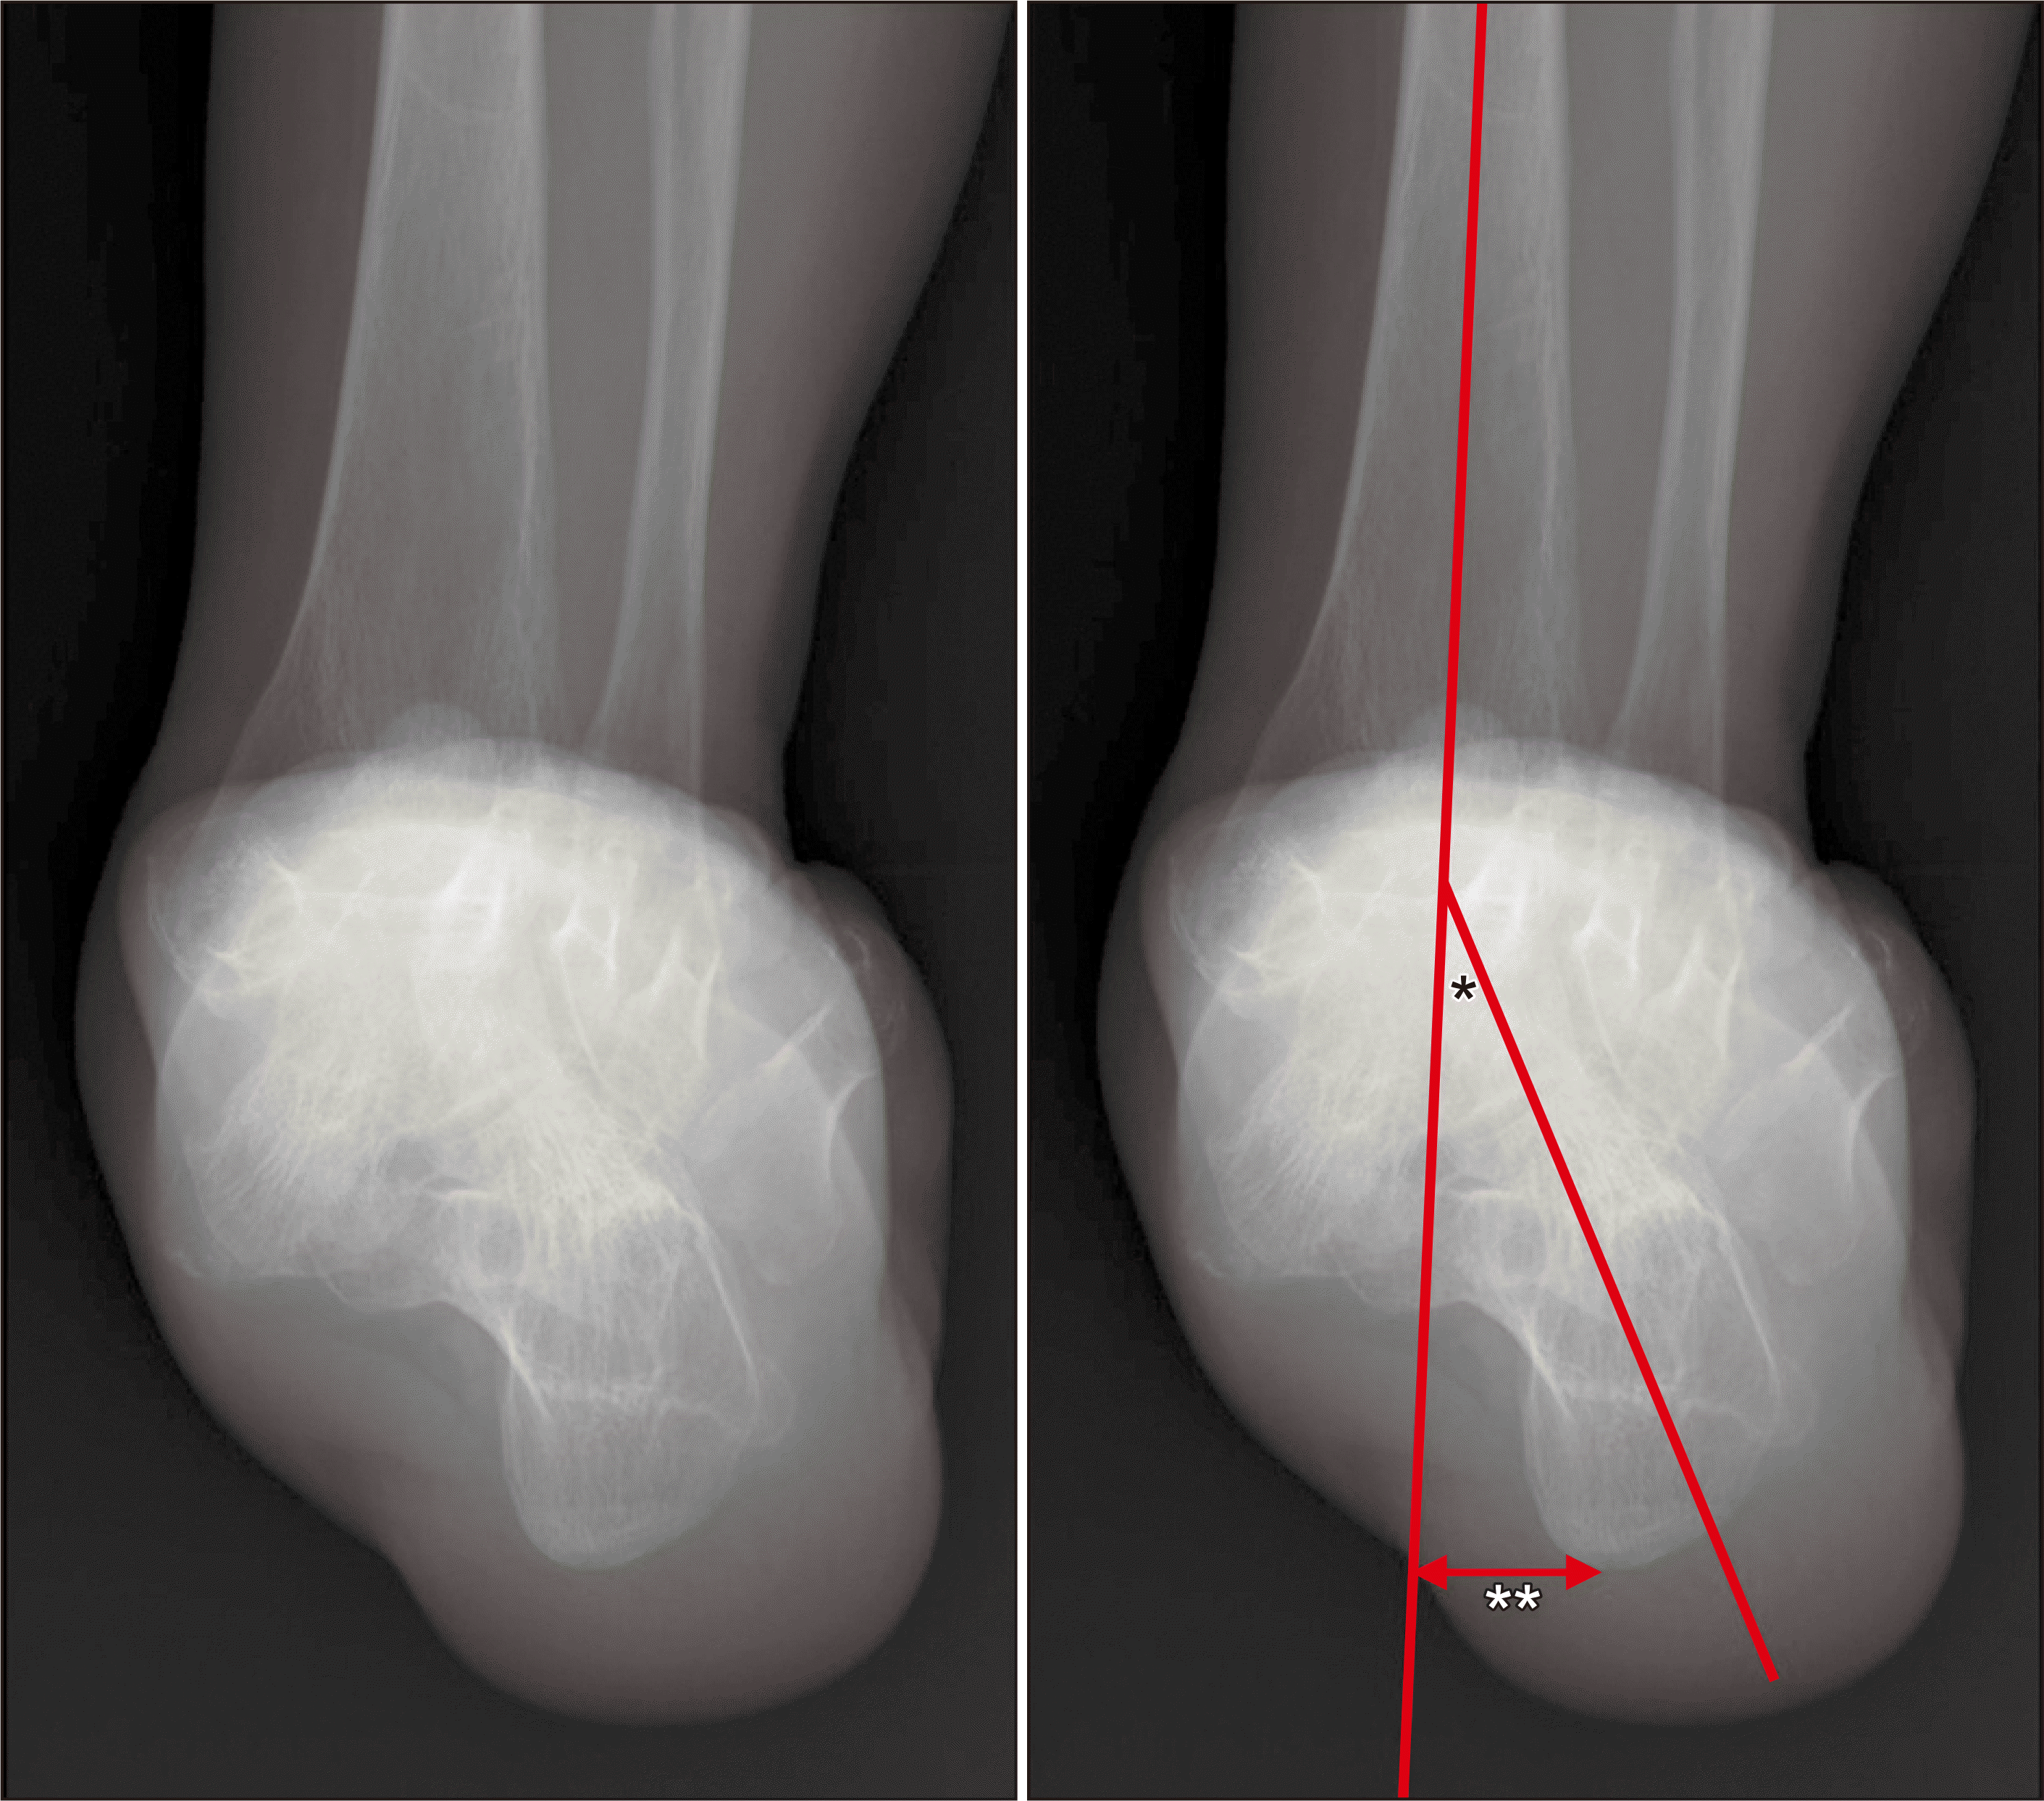

체중부하 방사선 촬영은 편평족의 진단에 있어 가장 표준이 되는 검사로, 체중부하 족부 전후면, 족부 측면, 족관절의 전후면 혹은 모티스 영상(mortise view) 및 후족부 정렬 촬영(hindfoot alignment view)8) 등이 진단을 위해 권고된다.9) 족부 전후면 사진에서는 전족부 혹은 중족부의 외전 정도를 평가할 수 있으며 거주상 관절 피복각(talonavicular coverage angle), 거주상 관절 이탈률(talonavicular uncoverage percent) 등 이를 반영하는 매우 다양한 지표를 측정할 수 있다(Fig. 1). 족부 측면 사진에서는 내측 세로궁의 소실 정도를 평가할 수 있는데, 흔히 쓰이는 지표로는 Meary angle이라 불리는 외측 거골-제 1중족골 각도를 측정할 수 있다(Fig. 2). 또한 족부의 내측주(medial column) 관절들의 족저부 벌어짐(plantar gapping) 정도를 확인하여 내측주 불안정성 정도를 평가할 수 있으며 족근동에서 거골과 종골의 직접적인 충돌 혹은 족근동 주변 골의 경화소견이나 낭종성 병변 등을 통해 족근동 충돌을 간접적으로 확인할 수 있다(Fig. 3). 족관절의 전후방 혹은 모티스 사진에서는 거골의 외반경사(valgus talar tilt)의 유무를 통해 족관절의 불안정성을 평가할 수 있으며 변형이 많이 진행한 경우 비골하 충돌 또한 확인할 수 있다(Fig. 4). 마지막으로, 후족부 정렬 촬영을 통해서는 후족부 외반 변형의 정도를 평가할 수 있는데, 주로 후족부 정렬각(hindfoot alignment angle) 혹은 후족부 모멘트암(hindfoot moment arm)을 측정한다(Fig. 5).10)

새로운 분류체계는 변형의 종류와 위치에 따라 A~E로 나누고, 각 변형의 유연성 유무에 따라 1기 유연성 변형과 2기 강직성 변형으로 분류하였다(Table 2).6) 이러한 변형은 진찰 소견과 체중부하 단순 방사선 촬영을 통해 평가하도록 하였고, 체중부하 전산화 단층촬영의 경우 아직 전세계적으로 사용되고 있지는 않기 때문에 판단기준에서 제외되었다. A형 변형은 후족부 외반 변형으로 후족부가 신체의 정중선으로부터 외측으로 전위된 변형을 뜻한다. 임상적으로 진찰 시 후족부 외반이 관찰되거나, 후족부 정렬 영상에서 후족부 정렬각 혹은 후족부 모멘트암의 증가 등으로 판단할 수 있다(Fig. 5). B형 변형은 전족부 혹은 중족부의 외전 변형으로 전족부나 중족부가 후족부를 기준으로 외측으로 전위된 변형이다. 체중부하 족부 전후면 사진상 거골두에 대한 주상골의 피복(coverage) 정도가 감소하고, 거주상 관절 피복각이 증가한다(Fig. 1). 또한 이 변형에 의해 족근동 충돌이 발생할 수 있으며, 족근동 주변의 압통 및 통증이 발생할 수 있다. 체중부하 족부 측면사진상 족근동에서 거골과 종골의 직접적인 충돌 소견이 보이거나, 족근동 주변의 거골과 종골의 골경화 혹은 골낭종 등을 통해 간접적으로 확인할 수 있다(Fig. 3). C형 변형은 전족부의 내반 변형 혹은 내측주 불안정성으로 임상적으로 후족부를 중립 위치에 고정한 뒤 관찰하였을 때 전족부가 내반을 보이는 변형이다(Fig. 8). 일부에서는 이를 회외 변형으로 불러야 한다는 의견도 있으나 현재 혼용해서 쓰이고 있다.11,20) 내측주 불안정성은 체중부하 족부 측면사진상 거주상 관절, 주상설상 관절(naviculocuneiform joint) 및 족근중족 관절(tarsometatarsal joint)이 배측 불안정증을 보이는 것으로, 영상검사상 족저부 벌어짐 유무 등을 통해 내측주 불안정성의 유무 및 위치를 확인할 수 있다(Fig. 3). D형 변형은 거근관절의 탈구 혹은 아탈구 변형으로 거골이 종골을 기준으로 내회전, 족저굴곡되면서 종골은 거골을 기준으로 외회전, 외반, 외측 전위가 발생하면서 거골하 관절의 아탈구가 발생하고, 심한 경우 비골하 충돌을 일으키게 된다(Fig. 4). E형 변형은 발목관절의 외반 변형이 발생한 경우이며, 족관절의 전후방 혹은 모티스 사진에서 거골의 외반경사로 확인할 수 있다(Fig. 4). 이 분류의 적용은 한 환자에 대해 A 부터 E까지의 변형 유무를 확인하고, 각각의 변형이 유연성 변형인지, 강직성 변형인지에 따라 1기와 2기를 나누는 방식으로 적용한다.

Williamson ER., Chan JY., Burket JC., Deland JT., Ellis SJ. 2015. New radiographic parameter assessing hindfoot alignment in stage II adult-acquired flatfoot deformity. Foot Ankle Int. 36:417–23. doi: 10.1177/1071100714558846. DOI: 10.1177/1071100714558846. PMID: 25380772.